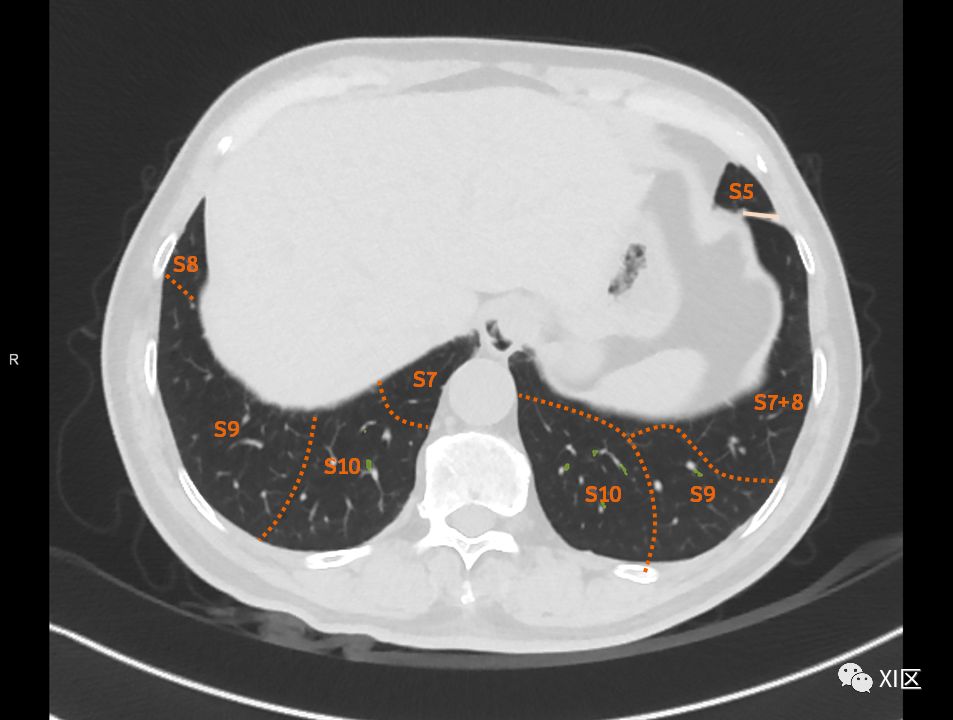

肺的断层分段示意图

在进行肺的分段时,可以上下观察浏览,沿着相应气管的走形可以更容易准确地进行分段。